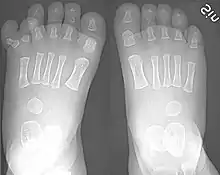

Classification is performed by using x-ray imaging to see the bone structures.[19]

Ulnar polydactyly

The classification of ulnar polydactyly exists of either two or three types. The two-stage classification, according to Temtamy and McKusick, involves type A and B. In type A there is an extra little finger at the metacarpophalangeal joint, or more proximal including the carpometacarpal joint. The little finger can be hypoplastic or fully developed. Type B varies from a nubbin to an extra, non-functional little finger part on a pedicle. According to the three-type classification, type I includes nubbins or floating little fingers, type II includes duplications at the MCPJ, and type III includes duplications of the entire ray.[38]

Radial polydactyly

The Wassel classification is the most widely used classification of radial polydactyly,[7] based upon the most proximal level of skeletal duplication. The most common type is Wassel 4 (about 50% of such duplications) followed by Wassel 2 (20%) and Wassel 6 (12%).[7]

Central polydactyly

The classification of central polydactyly is based on the extent of duplication and involves the following three types: Type I is a central duplication, not attached to the adjacent finger by osseous or ligamentous attachments; it frequently does not include bones, joints, cartilage, or tendons. Type IIA is a nonsyndactylous duplication of a digit or part of a digit with normal components, and articulates with a broad or bifid metacarpal or phalanx. Type IIB is a syndactylous duplication of a digit or part of a digit with normal components, and articulates with a broad or bifid metacarpal or phalanx. Type III is a complete digital duplication, which has a well-formed duplicated metacarpal.[20]